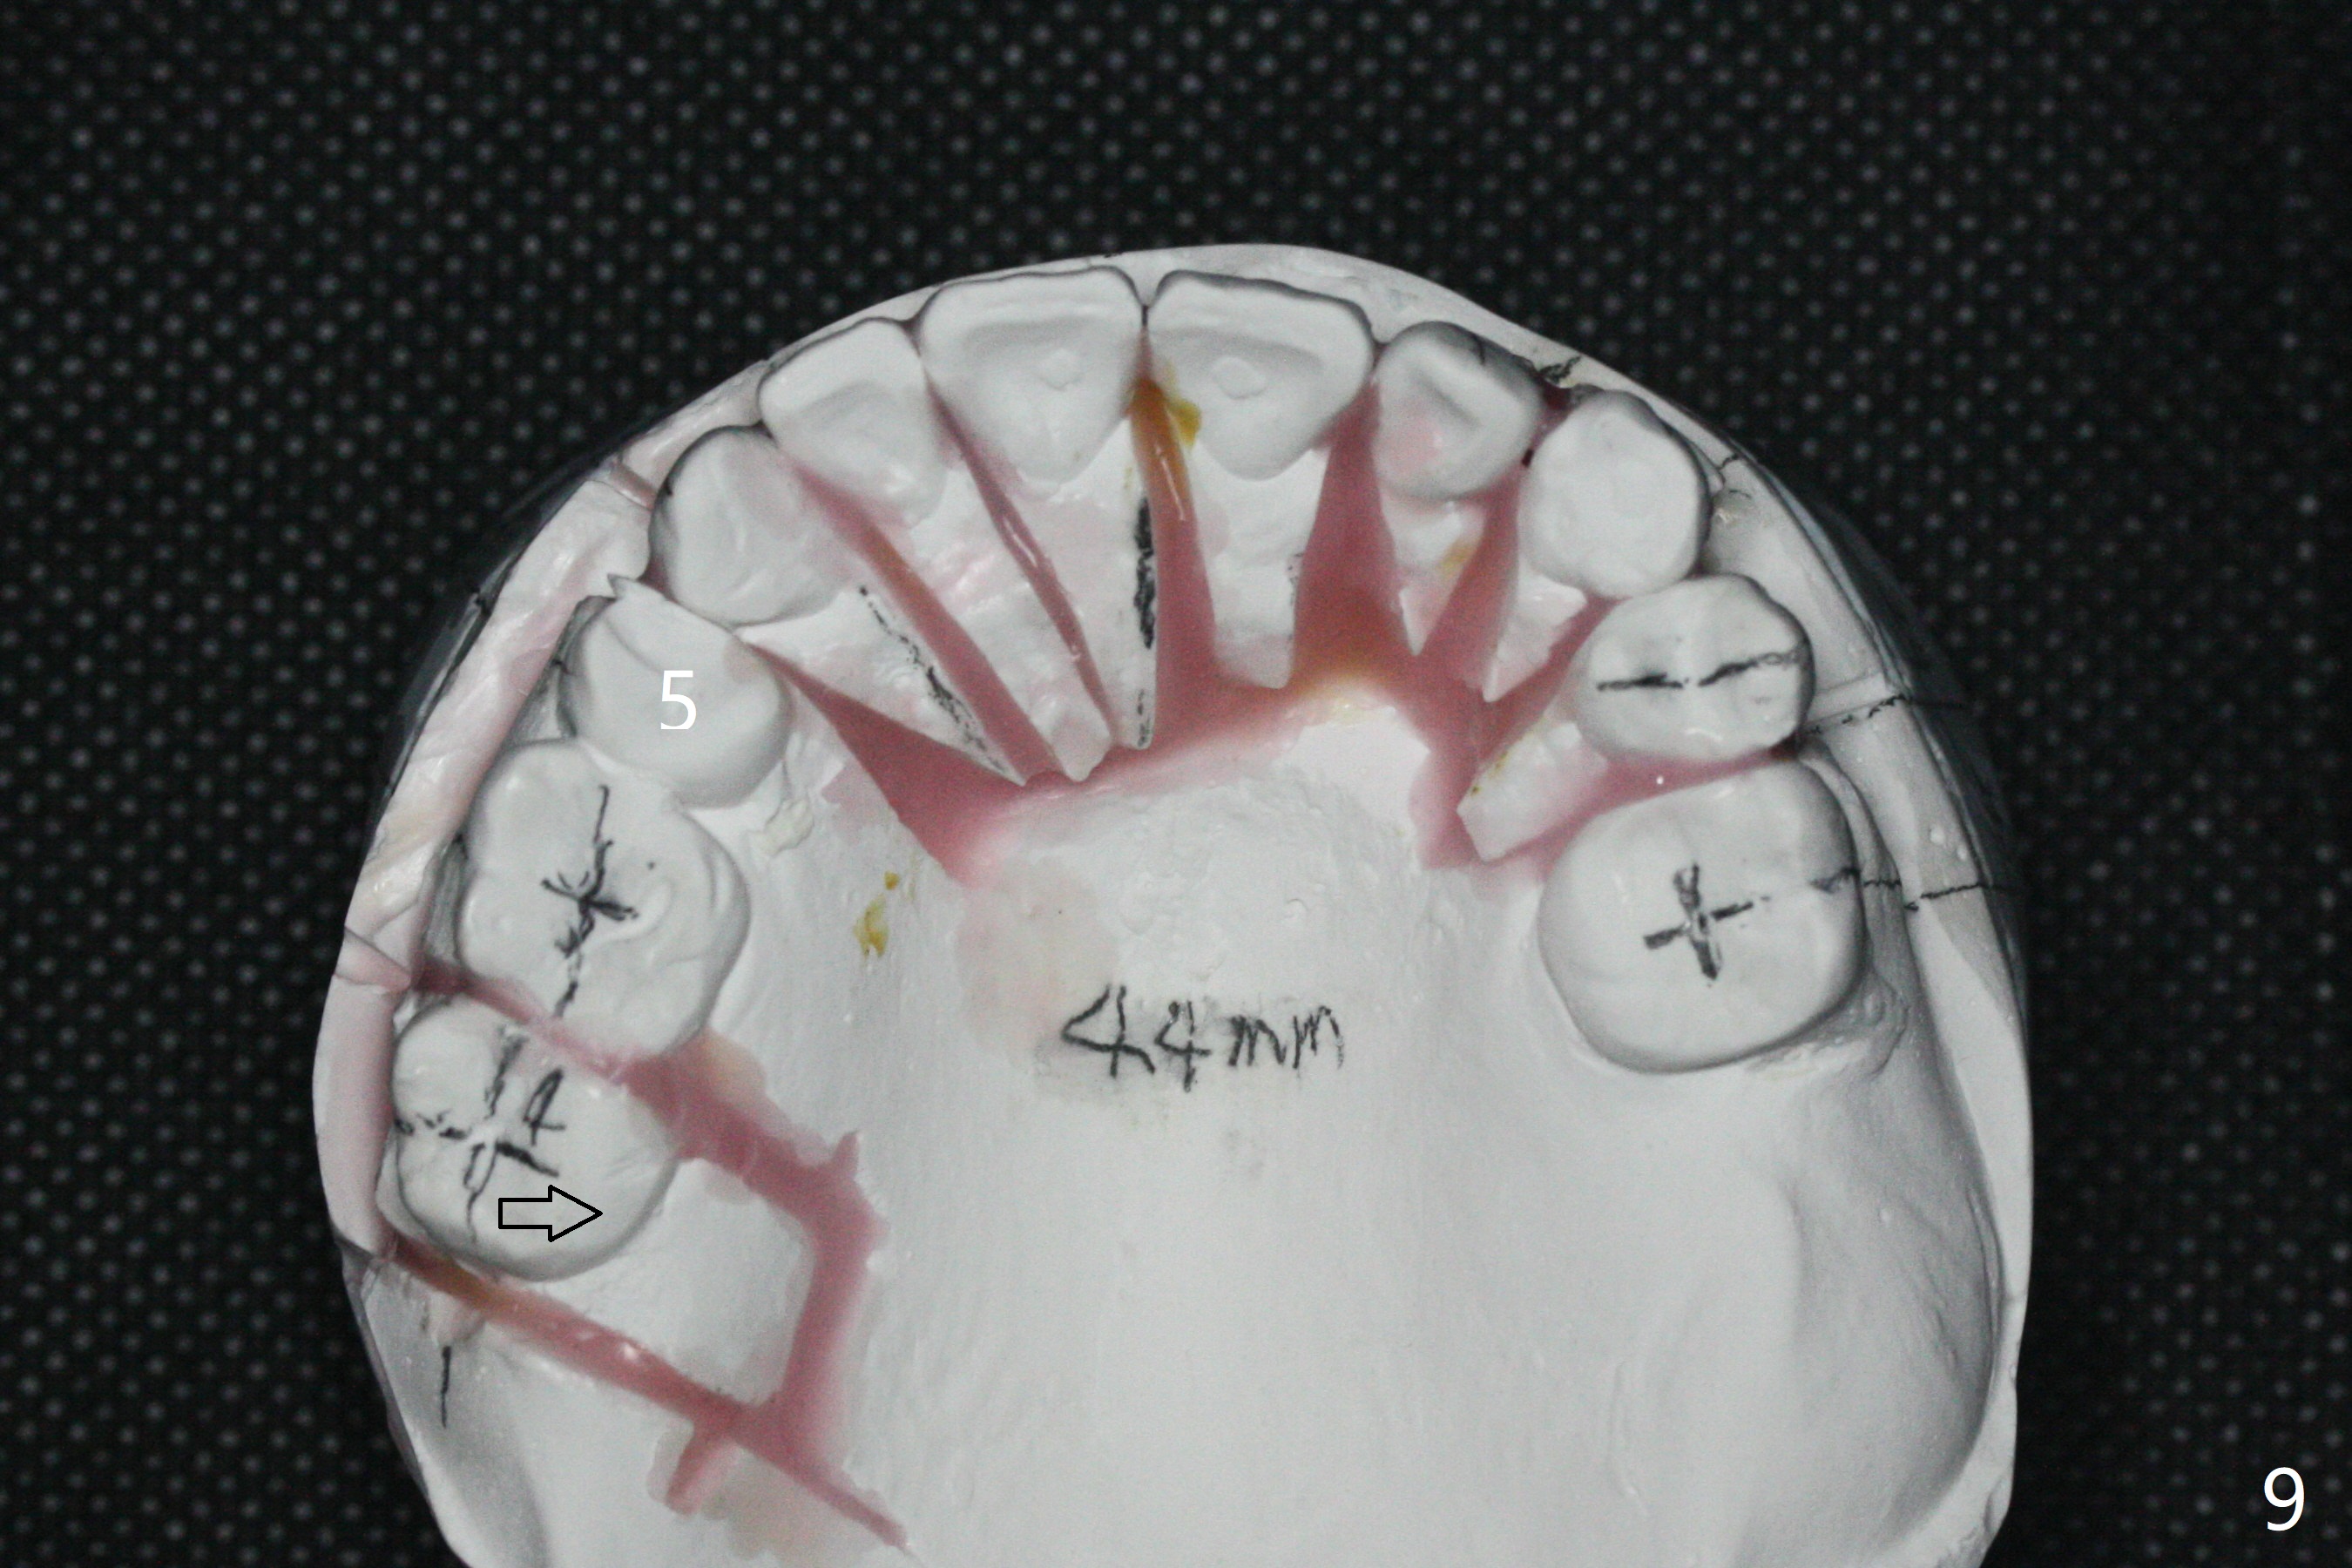

A 54-year-old man remains difficult in mastication in spite of implant placement at #14 and 31 (Fig. A, B, E, including screw loosening (poor trajectory at #14)). In addition to 2 more implants at #15 and 18 with guide, malocclusion seems to be necessary to be addressed (Fig.1-5). It appears that UR, LL4 should be extracted for orthodontic treatment (Fig.6-10). To reduce screw loosening, IS guide will be used to place IBS (5x9mm) and tissue-level (5x11mm) implants at #15 (PRF)and 18, respectively. If the one at #14 or 15 keeps loosening, splint #14 and 15 crowns. In fact the patient agrees with limited ortho (UR7 cross bite).